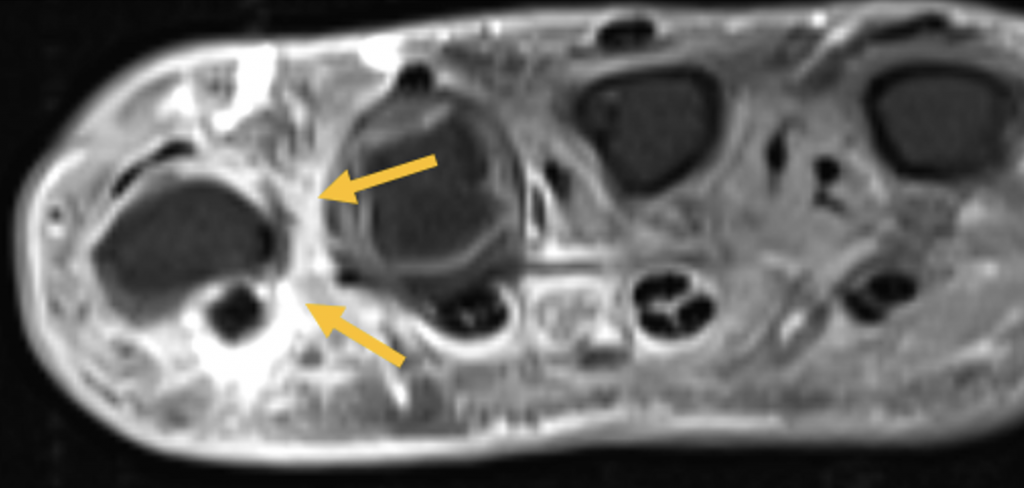

- Ausgeprägte Tenosynovitiden, v.a. der Flexorensehnen (Pfeile) (T1 FS KM)

- Synovitis der MCP D5, PIP und DIP Gelenke D5 (Pfeile) (T1 FS KM)

- Diffuses Weichteilödem entlang des 5. Strahles mit korrespondierender KM- Aufnahme (Pfeile) (T1 FS KM)

- Diffuses Weichteilentzündung eines ganzen Strahls – hier ist hauptsächlich der 5. Strahl betroffen, vereinbar mit einer klassischen Daktylitis